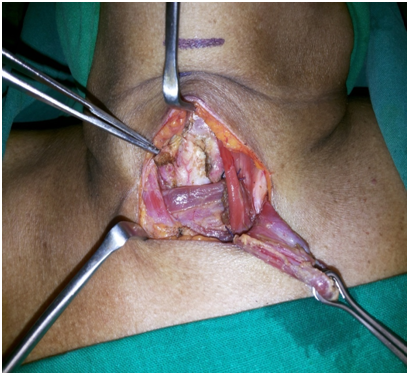

After identifying the landmarks (Figure 5) the neck was explored by a transverse 6 cm incision just on the upper border of the felt pulsation of the vessel. Skin, fat and platysmal incised and upper flap was raised to expose the investing layer of cervical fascia. The lower flap was deliberately not raised to prevent exposing the vessel. This fascia was split in the midline to expose the strap muscles and the isthmus of thyroid gland (Figure 6). The isthmus was split in midline and the edges transfixed to the ipsilateral Sternothyroid muscles (Figure 7). Both sides Sternohyoid muscles were cut at their upper ends, rotated and sutured to the other side (Figures 8&9) sternothyroids making a muscular bed over the horizontally running brachiocephalic trunk just underneath. An inverted “U” flap on the exposed 2nd to 4th tracheal rings was incised and was sutured to the unraised subcutaneous layer of the lower skin flap overlying the vessel hence forming another barrier and a bed for the tracheostomy tube so that it does not rub against it any of the time (Figure 10). Skin incision was closed leaving the opening for the trachoestoma. Portex cuffed tracheostomy tube with suction aid inserted after withdrawing the endotracheal tube.

Figure 6 Thyroid Gland and Trachea Exposed

Figure 7 Thyroid split

Figure 8 Strap muscle flaps raised

Figure 9 Strap Muscle Flap Bed

Figure 10 Inverted 'U' Flap Tracheostomy